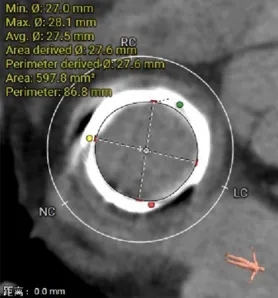

瓣架内径:27.6mm

瓣架外径:34.3mm

心室侧2mm:27.1mm

心室侧4mm:27.3mm

瓣架高度:21.2mm

neo-LVOT:604.2mm²

左室心肌厚度:3.9mm

选瓣依据:该二尖瓣原置换生物瓣型号未知,CT测量生物瓣瓣环周长折算直径约27.6mm,瓣架高度约21.2mm。